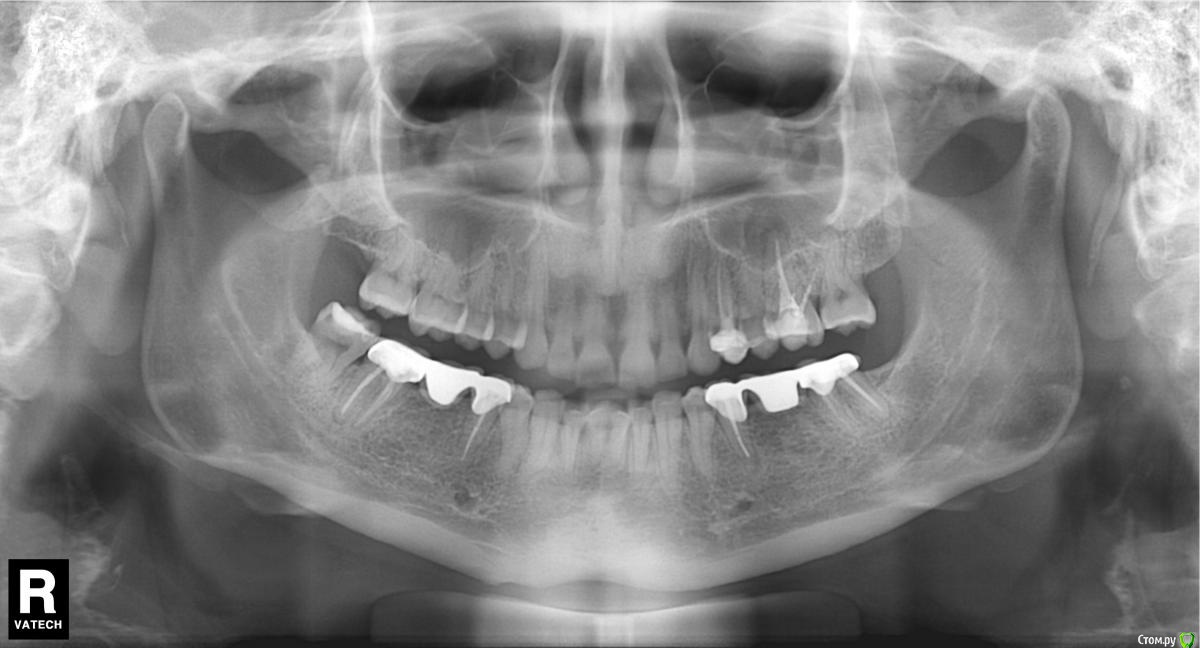

Дора Опубликовано 14 декабря, 2015 Поделиться Опубликовано 14 декабря, 2015 Добрый день! сегодня удалила зуб 26 из-за кистогранулемы. До этого стоматолог-терапевт предположил , что киста относится к 25 зубу. Хирург однозначно сказал, 26 и удалили. Когда удалил, я спросила про кисту , где она, но он даже не показал зуб. Сказал, что теперь организм все сам сделает! А я теперь думаю, может быть там не было кисты. скажите, дожно ли быть видно кисту, К какому зубу относится кистогранулема Прилагаю ОПТГ. спасибо Ссылка на комментарий

red_butler Опубликовано 14 декабря, 2015 Поделиться Опубликовано 14 декабря, 2015 На снимке периодонтит 2.6 зубаПочему не стали лечить? Ссылка на комментарий

Ker Опубликовано 14 декабря, 2015 Поделиться Опубликовано 14 декабря, 2015 (изменено) Два года мучаюсь полипозным риносиситом. Сделала 2 операции. А этот зуб был сначала лечен 7 лет назад. появилась боль при накусывании. Перепломбировали каналы 4 года назад. боль оставалась, врач развел руками. Потом начались лор - проблемы. После первой операции через 11 месяцев все вернулось - полипы и в пазухах образование грибкового муцина. Аллергия, предполагаемая врачем. на грибы - тесты 0. Сделала ОПТГ - нашли кистогранулемы, сказали срочно удалять. Мне важно сейчас знать, точно ли это 26 зуб и где киста, ее должны были удалить. От врача ничего не добилась.Кисты нет, есть периодонтит.Всё заживёт теперь уж.Да, 26 зуб. Изменено 14 декабря, 2015 пользователем Ker Ссылка на комментарий

red_butler Опубликовано 14 декабря, 2015 Поделиться Опубликовано 14 декабря, 2015 Спасибо. неужели такой важный зуб можно было сохранить? и лор, и стоматалог в один голос - кистогранулема, не лечить, а удалять.Если судить только по снимку, то да, зуб можно было сохранить. Ссылка на комментарий